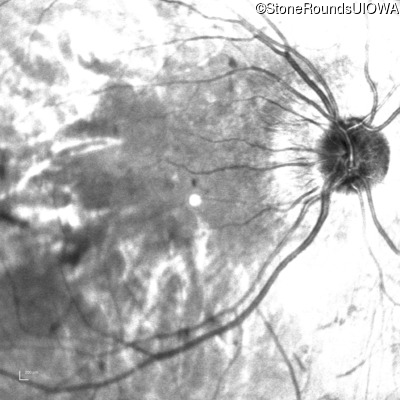

Infrared Fundus Photograph - Left - 5/160

Exemplar